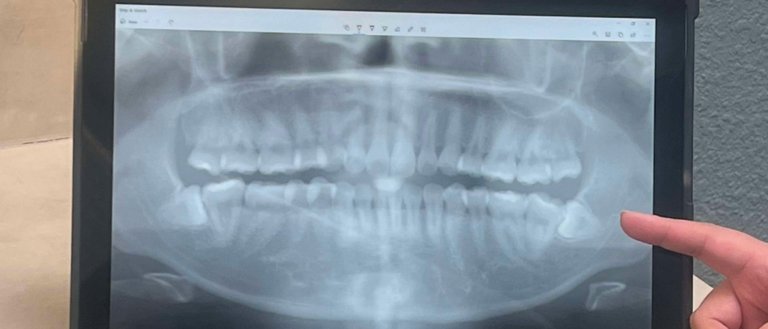

February 6, 2023 Why Remove Impacted Wisdom Teeth? What Are Wisdom Teeth? Wisdom teeth are the last teeth that develop